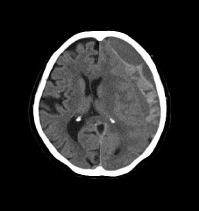

MRI/CTで分かる疾患症例

MRI検査

内科領域